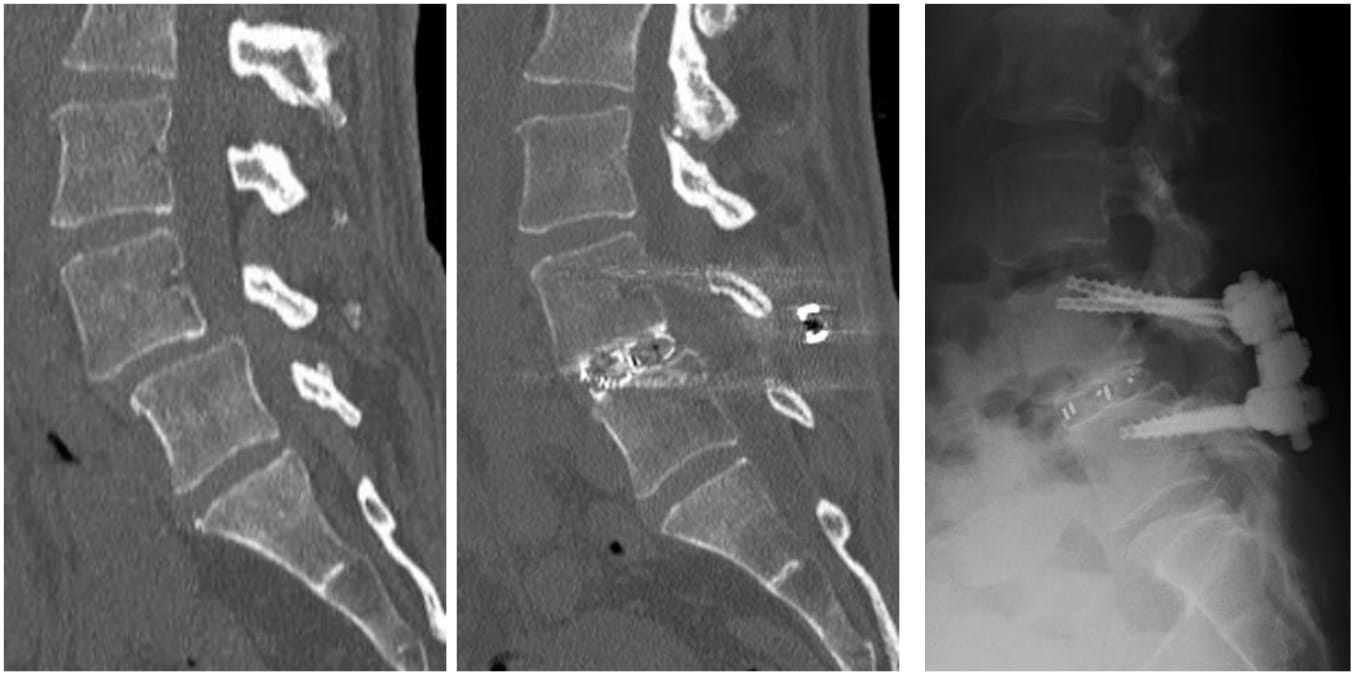

図3-1.MIST法による腰椎固定術の例

図3-2.腰椎すべり症に対する固定術の例 出来るだけ小切開で行うようにしています